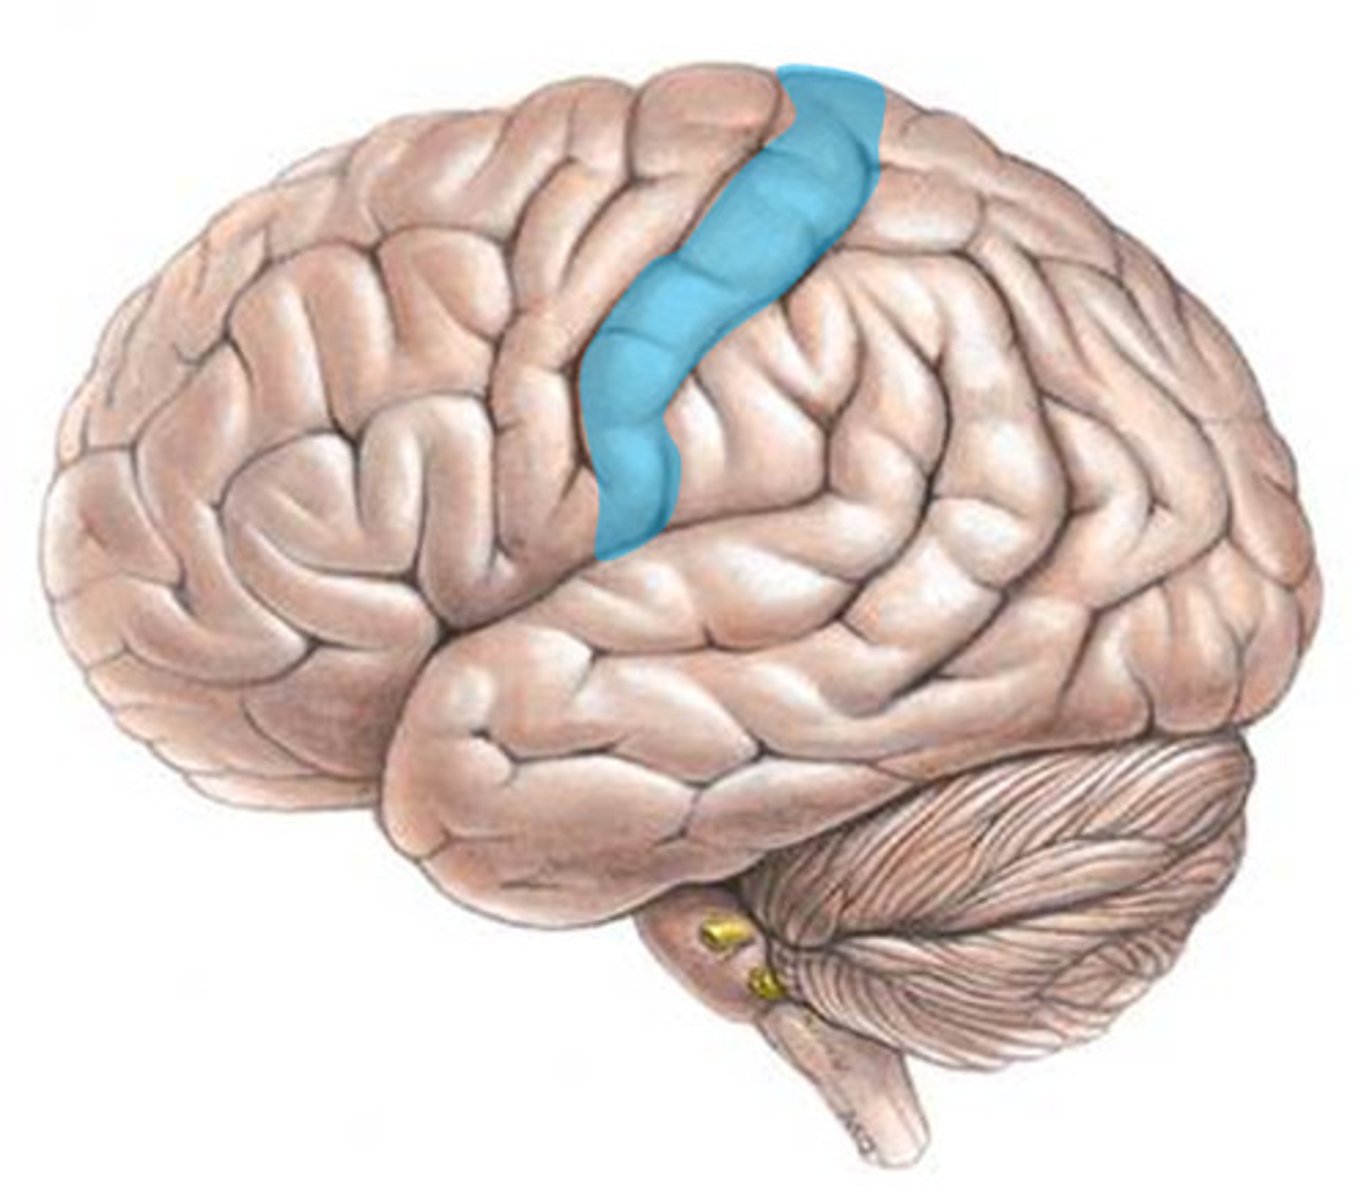

primary somatosensory cortex

•Located in postcentral gyrus of parietal lobes

•Receives somatic sensory information from

•Proprioceptors, touch, pressure, pain, temperature receptors

postcentral gyrus

the strip of parietal cortex, just behind the central sulcus, that receives somatosensory information from the entire body

central sulcus

separates frontal and parietal lobes